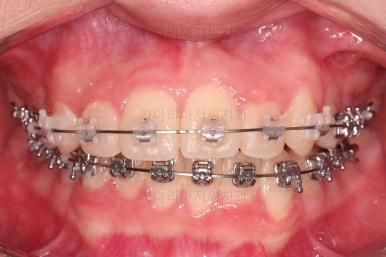

장치 부착 직후의 얼굴모습입니다.

입 다문 모습이 약간 불편한 느낌이지만 큰 차이는 없고요.

웃는 모습에서 아랫니가 보이는 타입이라 메탈장치가 보이기는 하는데요.

확실히 윗니의 세라믹이 더 심미적이긴 하죠.

비교적 조기에 앞니는 가지런해졌고요.

대신 교합이나 기울어진 느낌 등 디테일을 맞추기 위한 작업을 추후에 계속 하게 됩니다.